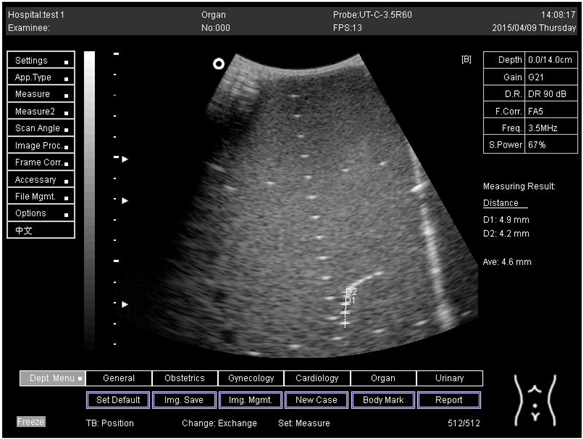

Table A3. The distance for axial and lateral resolution in mm for depth of 14.0, 16.0, 18.0 and 24.0 cm depth for curve probe at surface 4.

Depth (cm)DiagramDistance (mm)

14.0Axial resolution

Biomimetics 07 00130 i023

D1 = 4.9

D2 = 4.2

Lateral resolution

Biomimetics 07 00130 i024

D1 = 5.0